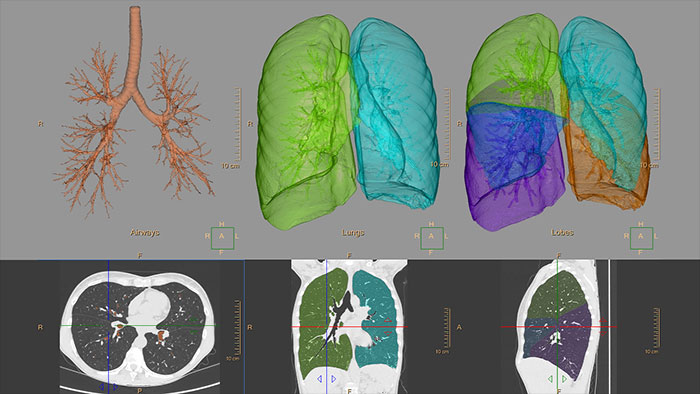

CT COPD

Quantify diffuse lung disease

CT COPD helps visualize and quantify the destructive process of diffuse lung disease (e.g. emphysema). The application provides a guided workflow for airway analysis, reviewing and measuring airway lumen, and assessing air trapped.

Benefits

- Automatic lung and lobes segmentation.

- Automatic airway extraction, airway tree segmentation and navigation path extraction, enabling the measurement of airway parameters such as lumen diameter and wall cross-section.

- Tools for qualitative and quantitative temporal comparison of up to four follow-up studies in order to determine the progression of the disease.